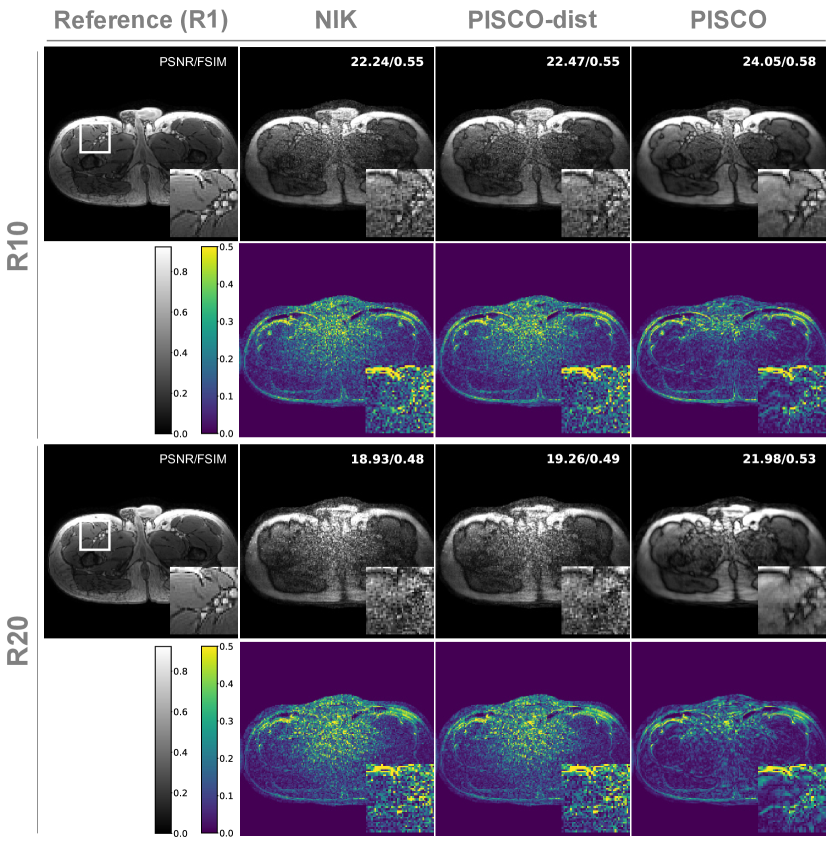

Upper leg Quantitative and qualitative results are visualized in Fig. 4 for two acceleration factors. NIK’s reconstruction performance noticeably degrades with increasing acceleration, i.e. reduced amount of training data. PISCO-dist marginally improves reconstructions and metrics, but remains noisy. In contrast, the proposed PISCO results in less noisy reconstructions than both, NIK and PISCO-dist. Also, it recovers vessel details more reliably, represented in higher PSNR and FSIM, respectively. Again, no temporal redundancy is leveraged yet.